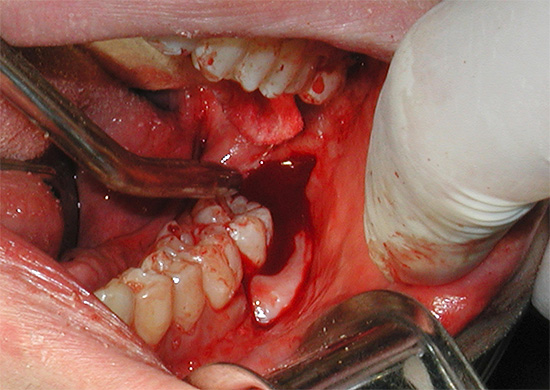

Em segundo lugar, o paciente, imerso em sono profundo, não pode seguir as instruções do médico, tornando seu trabalho mais conveniente (pelo menos básico para abrir mais a boca para que haja melhor acesso ao dente problemático). Portanto, o médico é forçado a mudar constantemente a posição do seu corpo para reduzir a carga nos músculos, o que leva à fadiga rápida. Mas todos entendemos que, por exemplo, com uma remoção longa e difícil de um dente do siso, a fadiga do médico não aumentará seu trabalho de qualidade: em algum lugar sua atenção diminuirá, em algum lugar ele poderá escolher uma opção mais rápida e fácil, mas também mais traumática para o procedimento. . Existem muitas oportunidades ...

- A capacidade de realizar operações longas e complexas para remover um ou mais dentes, especialmente nos casos em que os dentes têm uma estrutura complexa e uma posição incorreta na mandíbula. Isto é especialmente verdade. ao remover os dentes inferiores da sabedoria, uma vez que a estrutura e a localização desses dentes na mandíbula são absolutamente imprevisíveis.

“Ontem, o dente do siso inferior foi removido sob anestesia geral. A operação durou aproximadamente 40 minutos, como fui informado. Os médicos disseram que na foto meu dente estava enraizado no próximo, então eu tive que cortá-lo por um longo tempo e retirá-lo em pedaços. Eu certamente não teria sobrevivido a esse espetáculo em minha mente, e eles me fizeram dormir bem, então não ouvi ou vi nada. O único ponto negativo é o desagradável catador de anestesia, e havia uma boca seca e terrível, pois após uma ressaca severa, minha cabeça estava zumbindo por algumas horas, mas está tudo para trás. Estou satisfeito que tudo correu bem. "